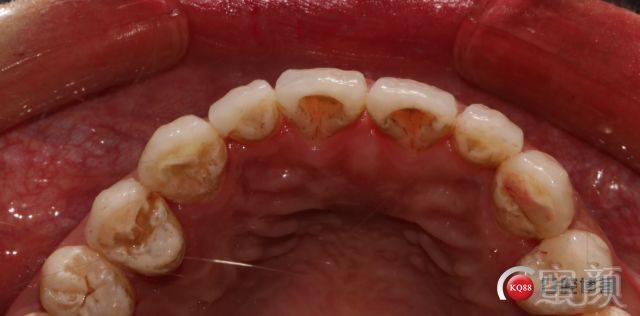

很久没有做美学修复案例了;因为还是病例适应症选择比较纠结;该患者也是前期多方会诊排除智齿;正畸老师会诊后和患者沟通对于中线不要求对称才去做;包括牙周;牙龈炎的前期治疗;原树脂修复的导致牙龈红肿退缩;都经过了2个月的治疗后观察期才取模制作蜡型;沟通无误后才进行牙体预备;但凡患者有不明白;有疑问;都在备牙之前交流解释清楚。

唯一的调整是因为去除树脂后切端的牙体发黑所以从开窗式的修复方案改为对接式。包绕式。